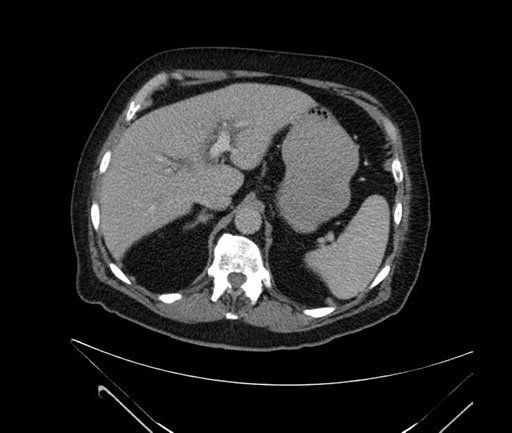

Imaging Analysis

Look through the patient's CT scan to identify any areas of concern for the necessary procedure.

Based on your CT findings, which issue(s) would give reason for "planned slowing down moment(s)" in this case?

Considering a standard Whipple procedure, what step(s) of the operation would you do differently in this case?